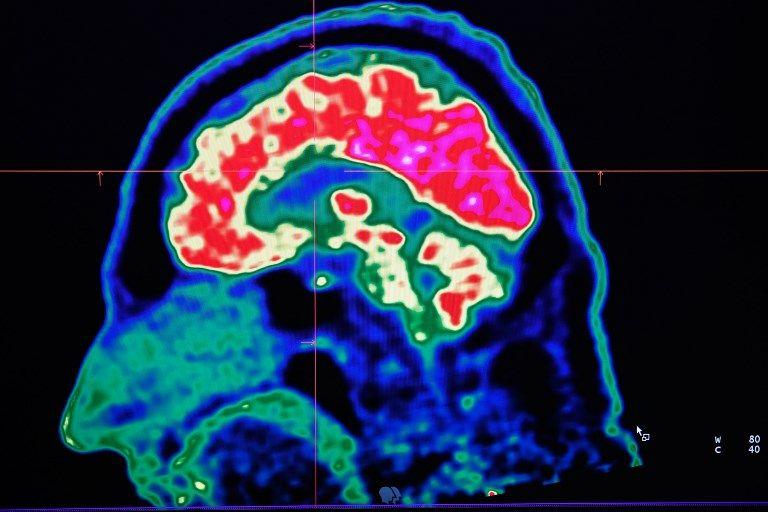

Cela ressemble à de la science-fiction, mais les progrès actuels de la médecine, principalement en neurologie, poussent de nombreux professionnels à tirer la sonnette d'alarme : notre cerveau doit être protégé contre les dangers qui le menacent dans un futur proche.